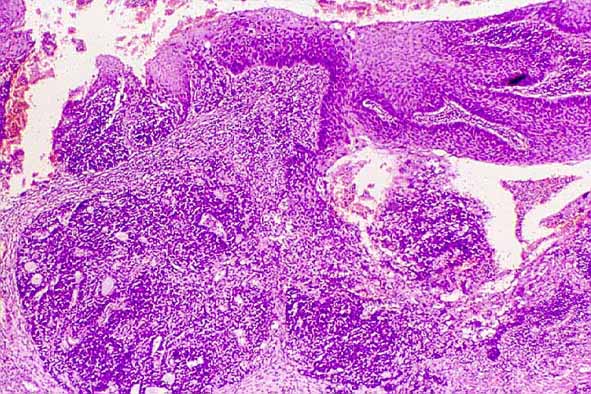

Figura 3. Material eosinofilo tipo membrana basal (H E, x 40).

Figura 4. Células con núcleos hipercromáticos, leve pleomorfismo y presencia de numerosas figuras mitóticas (H E, x 400).